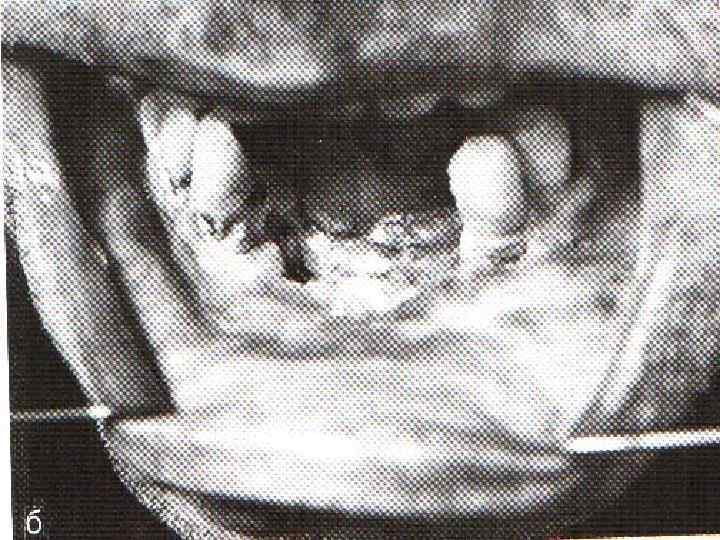

Рак слизистой оболочки альвеолярного края челюстей Ранний симптом – зубная боль! Немотивированное удаление зуба способствует распространению опухоли в зубную лунку, затем в кость! В начальном периоде при дотрагивании кровоточит. Инфильтрация подлежащей костной ткани – позднее проявление болезни!

Рак слизистой оболочки альвеолярного края челюстей Ранний симптом – зубная боль! Немотивированное удаление зуба способствует распространению опухоли в зубную лунку, затем в кость! В начальном периоде при дотрагивании кровоточит. Инфильтрация подлежащей костной ткани – позднее проявление болезни!

Рак альвеолярного отростка верхней челюсти

Рак альвеолярного отростка верхней челюсти